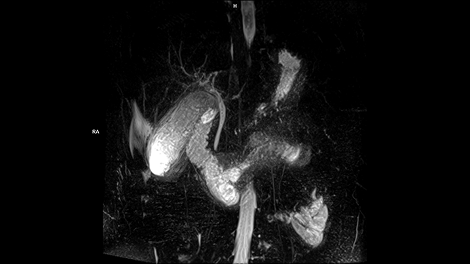

Whether it is head, neck, spine, abdomen or MSK – our clinical experts have complete confidence in the ability of MAGNETOM Free.Max to deliver excellent diagnostic quality for all these standard clinical MRI applications.